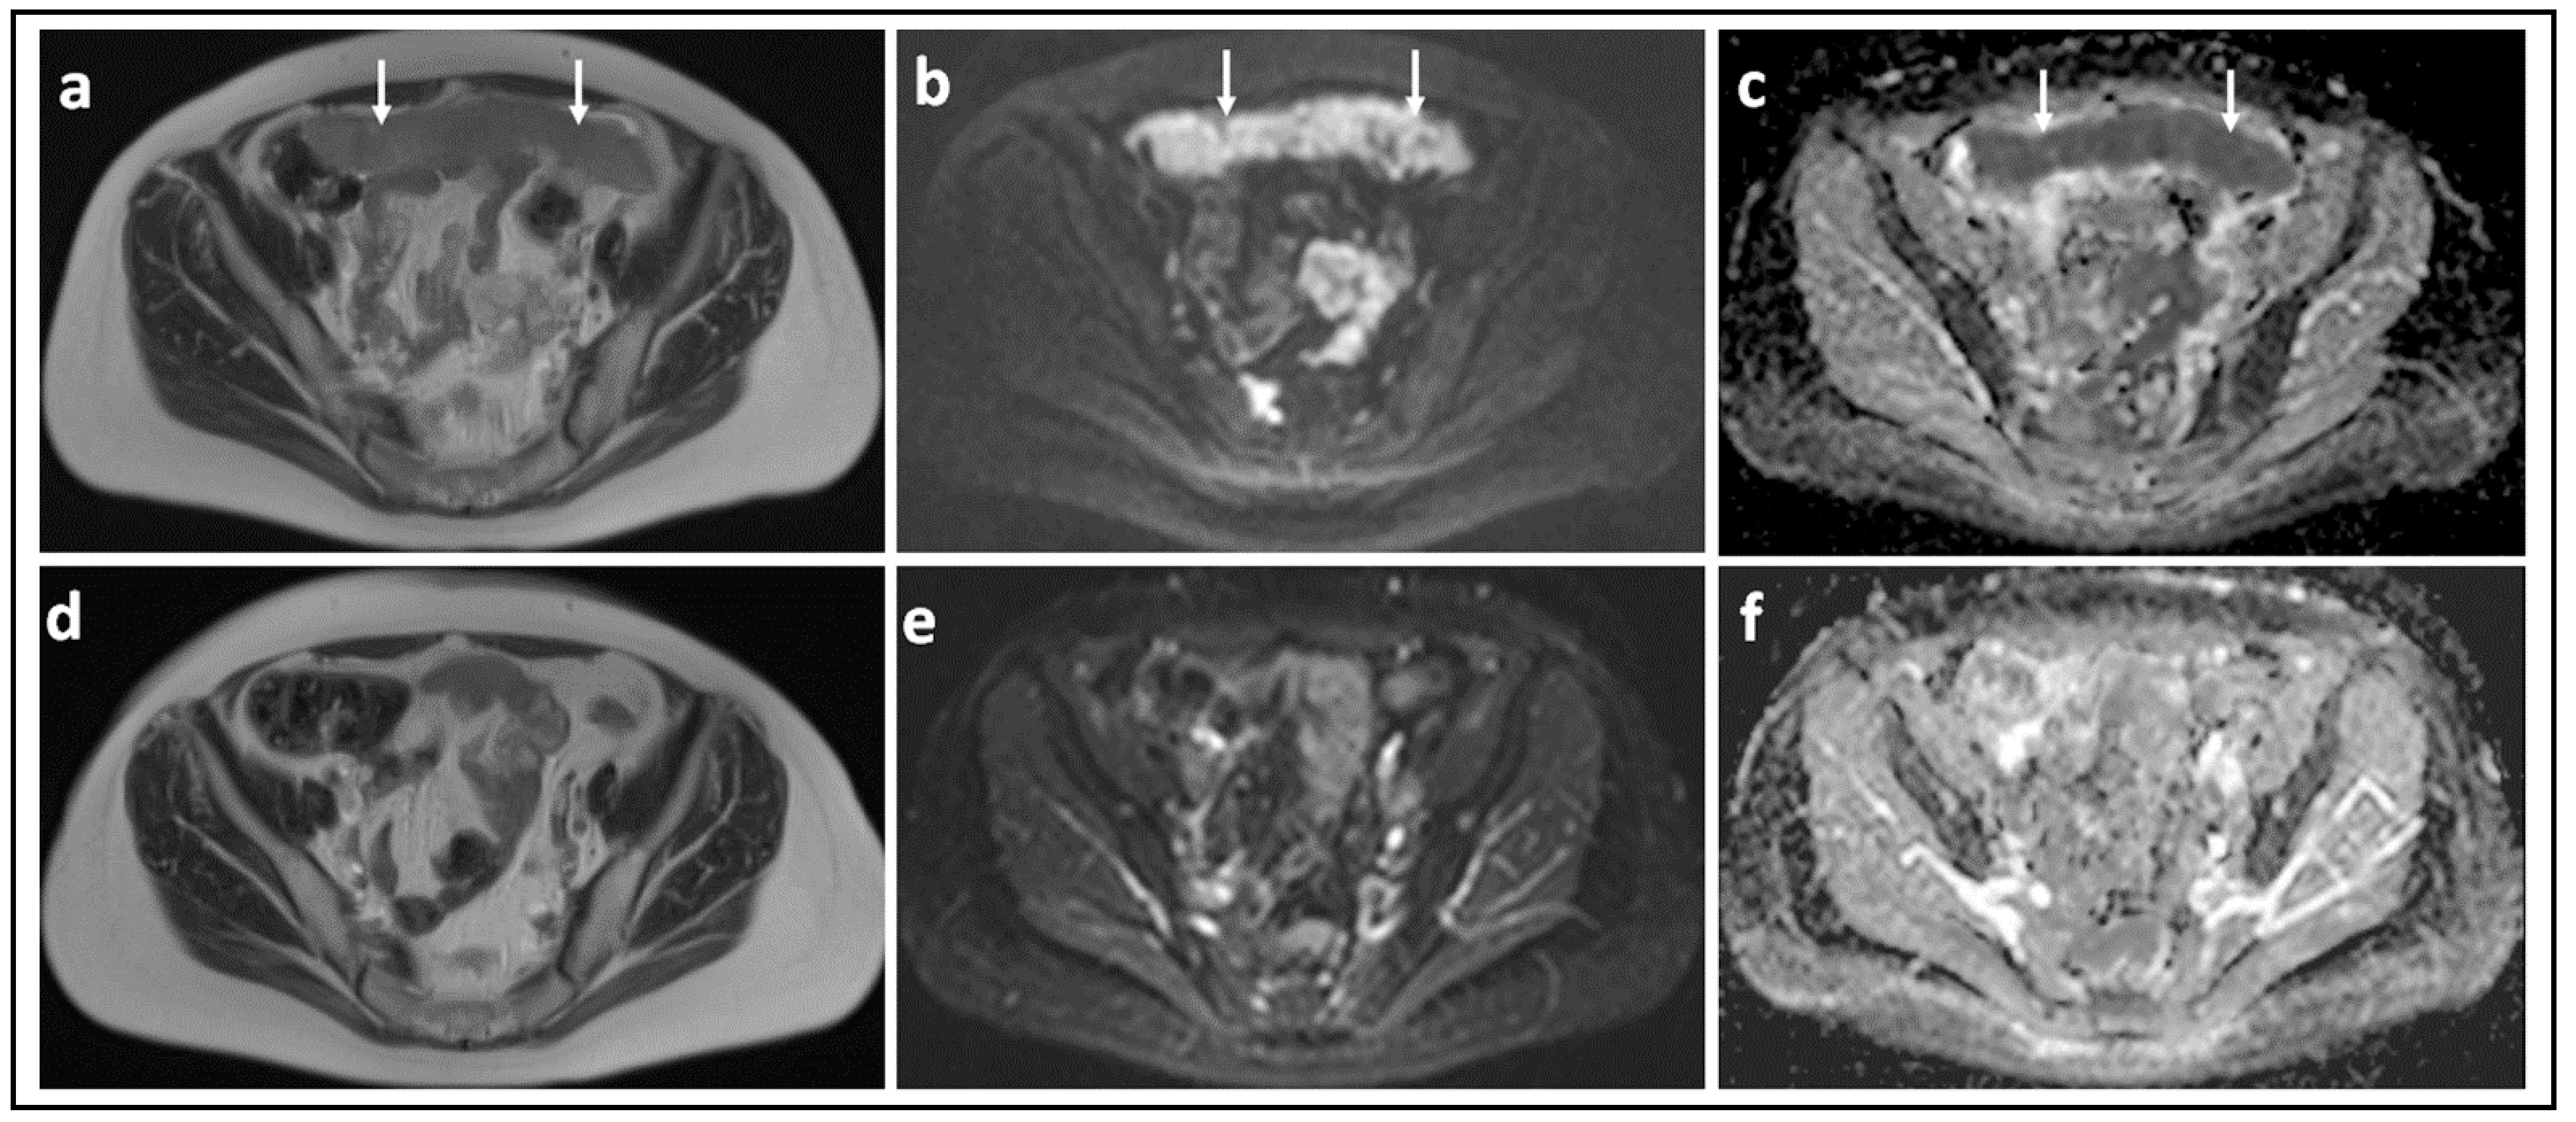

- Winfield, J.M.; Wakefield, J.C.; Dolling, D.; Hall, M.; Freeman, S.; Brenton, J.D.; Lutchman-Singh, K.; Pace, E.; Priest, A.N.; Quest, R.A.; et al. Diffusion-weighted MRI in Advanced Epithelial Ovarian Cancer: Apparent Diffusion Coefficient as a Response Marker. Radiology 2019, 293, 374–383. [Google Scholar] [CrossRef] [PubMed]

- Winfield, J.M.; Wakefield, J.C.; Brenton, J.D.; AbdulJabbar, K.; Savio, A.; Freeman, S.; Pace, E.; Lutchman-Singh, K.; Vroobel, K.M.; Yuan, Y.; et al. Biomarkers for site-specific response to neoadjuvant chemotherapy in epithelial ovarian cancer: Relating MRI changes to tumour cell load and necrosis. Br. J. Cancer 2021, 124, 1130–1137. [Google Scholar] [CrossRef] [PubMed]

- Kyriazi, S.; Collins, D.; Messiou, C.; Pennert, K.; Davidson, R.; Giles, S.; Kaye, S.B.; DeSouza, N.M. Metastatic Ovarian and Primary Peritoneal Cancer: Assessing Chemotherapy Response with Diffusion-weighted MR Imaging—Value of Histogram Analysis of Apparent Diffusion Coefficients. Radiology 2011, 261, 182–192. [Google Scholar] [CrossRef] [PubMed] [Green Version]